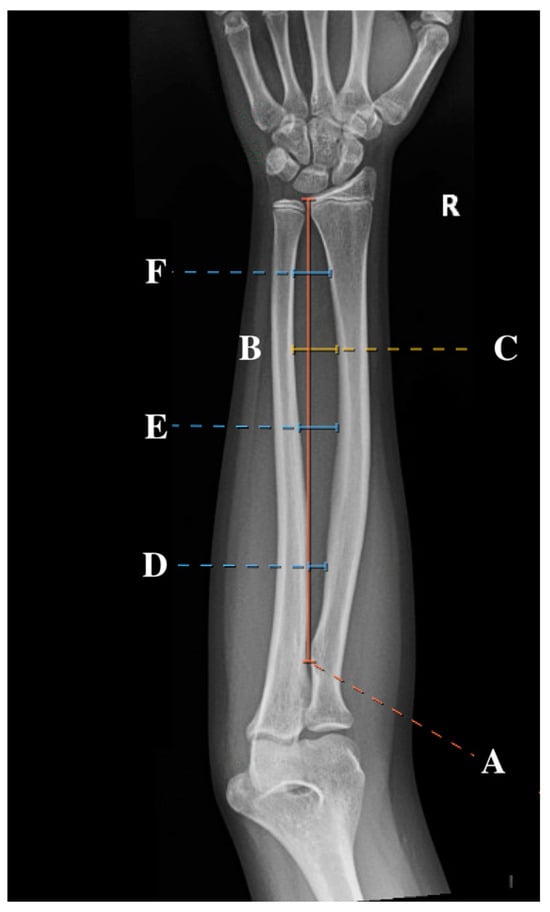

Standard AP radiographs were obtained from the IMPAX imaging system. Subsequently, the IMPAX imaging system measuring tool was used to measure the location of the maximum radial bow, as initially described by Schemitsch and Richards [4,7]. Measurements also included the total radial length (measured as the distance between the biceps tuberosity and the distal radial ulnar joint (DRUJ)), location of maximal radial bow (measured as both the distance from biceps tuberosity to the apex of the radial bow and the percentage of total radial length), and depth at maximal radial bow (measured both as the distance from the cortex of the radius at the maximum bow to the cortex of the ulna and as the percentage of total radial length). These measurements, represented as a percentage of the total radial length, were utilized to normalize the values to allow for comparison across age groups, similar to the methodology employed in previous studies [2,4,10]. In addition to these previously described measurements, the location of the proximal, middle, and distal third of the radial bow was recorded. A sample of the measurements can be found in Figure 1. All measurements were performed by four observers (SK, RL, CM, and AF) to improve generalizability to other surgeons.

Figure 1. An AP radiographic view of the forearm of a 12-year-old female with the six measurements included in this study: total radial length (A), location of the radial bow (B), maximum radial bow (C), and proximal (D), middle (E), and distal (F) radial bow.